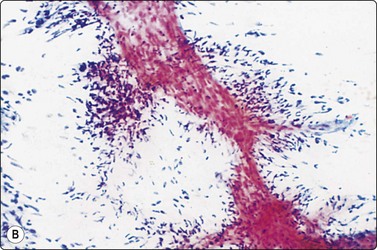

image image

Fig. 8.6 Caseation necrosis

(A) Amorphous and granular debris with neutrophils (H&E, MP); (B) Single-cell pattern of necrosis (H & E, HP).

Epithelioid histiocytes are fairly cohesive and form granulomas which are often aspirated intact (Fig. 8.5). Epithelioid cells have an elongated or bean-shaped nucleus and abundant cytoplasm which is rather pale and indistinct both in Pap- and H & E-stained specimens (Fig. 8.5). The cytoplasmic density is higher in MGG-stained material. Multinucleated histiocytes can be seen but are usually sparse. They are mainly free of intracytoplasmic pigment or birefringent material, unlike the multinucleated histiocytes seen in non-specific reactions in pulmonary tissue. Caseous necrosis has a variable appearance. There may be an amorphous to granular background with little cell outline visible, but sometimes outlines of necrotic cells may be prominent (Fig. 8.6) and often the appearances are merely of nondescript debris, histiocytes and neutrophils. Dahlgren cites granular calcific material as a common accompaniment.98 Lymphocytes may be plentiful in granulomatous inflammation.

Necrotic tumor may be homogeneous or granular and closely resemble caseous material. Conversely, we have seen cases of tuberculosis where ghost outlines of single cells were distributed across the smear and closely mimicked necrotic tumor (Fig. 8.6).